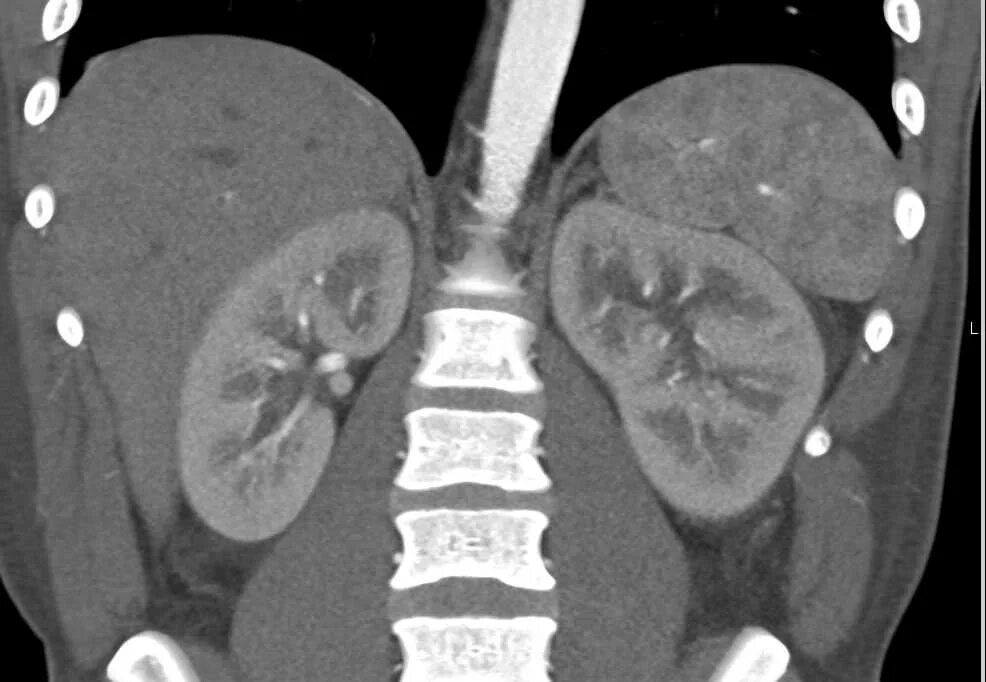

Пиелонефрит кт